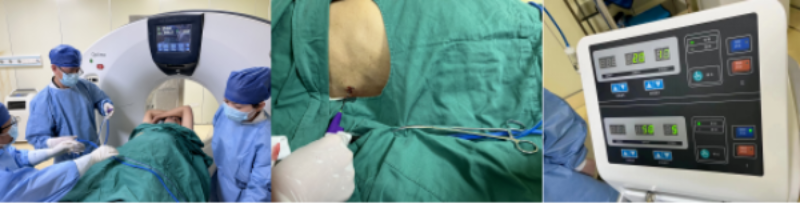

肝肿瘤邻近横膈,穿刺难度大,术前徐稳深主任带领肿瘤科专业团队及放射科房志杰医生为患者进行精准定位,设定穿刺路线

CT引导下微波消融治疗过程